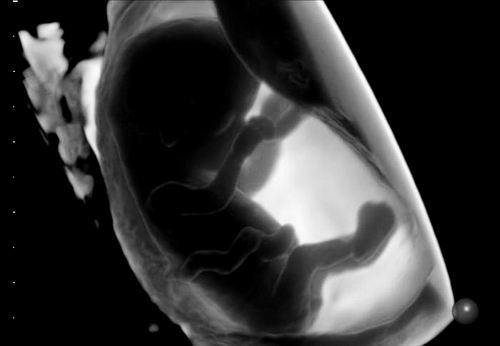

通过3D宫腔超声检查获得的11周胚胎影像。图片来源:Generation R study group

研究人员在孕7周、9周和11周时,通过经阴道超声测量了胚胎的头臀长(CRL)及卵黄囊体积。论文第一作者、伊拉斯姆斯大学的Celine Lin表示:“我们观察到,女性摄入超加工食品与不孕风险、备孕时长并不总是相关,但与孕7周的胚胎生长略缓、卵黄囊偏小有关。这些早期发育差异虽小,但从科研和人口层面来看意义重大。我们首次证实,超加工食品不仅关乎孕妇健康,还与后代发育相关。”